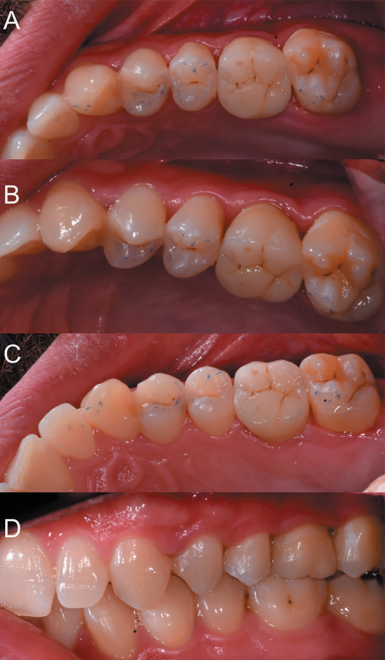

After 2 months, a new clinical review (Figure 17) and a radiograph was performed by a periapical radiograph (Figure 18), proceeding to remove the ferulization. After 3 months, another clinical review (Figure 19)

and a radiograph was performed by parallel periapical radiograph (Figure 20), where an adequate bone formation can be observed around the transplanted tooth.

autotransplant, coinciding with the duct treatment.

autotransplant.

palatine (C), occlusion (D).